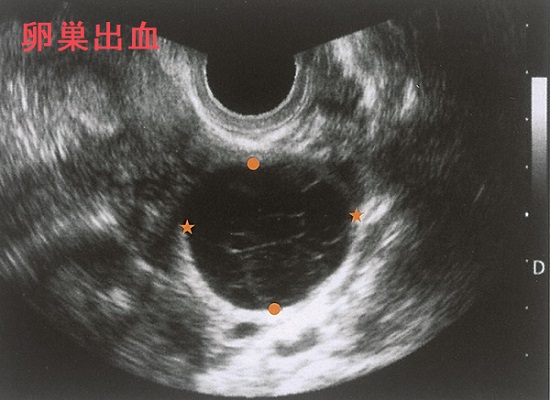

不正性器出血は、通常の生理(月経)以外でおきる性器からの出血です。不正性器出血の原因は

- 妊娠関連(最も多い);流産、異所性妊娠(子宮外妊娠)、胞状奇胎が考えられ、妊娠反応検査(尿hCG定性検査)が必要